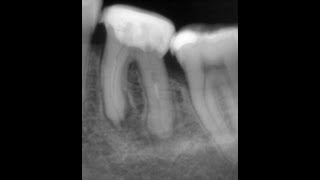

Вебинар №7 - Мифы и легенды антимикробной обработки корневых каналов. Заблуждения большие и малые.

Предидущий веб -    • Вебинар №6 - Микробиология корневых канало...   Следующий веб -    • Вебинар №8 - Прикладное применение знаний ...   1.Воздействие эндодонтических ирригантов на микрофлору. Антибиотики в каналах, йодоформ, электрофорез. 2.Восприимчивость Грамм+ и Грамм- микробов к ирригантам. Эфективность гидроокиси. 4. Действие хлоргекседина на вторичную инфекцию. 5 Антибиотики в канале. Биопленка как доказательство неэффективности.Резистентные штаммы. 6. Йодоформ — спектр действия. Масло в канале. 7. Блеск и нищета депофореза. Хороший антимикробный эффект и пустой канал.Научное обоснование. Вебинар напрямую посвящен наименее эффективным методикам антисептической обработки и заблуждениям, существующим в тот или иной период времени, и сохранившимися до сих пор. В том числе представлено научное обоснование современных методик и механизмы действия антисептиков. Это объясняет их выбор в тех или иных клинических ситуациях. 7й вебинар из 8и, образующих 16ти часовой курс по первичной эндодонтии.